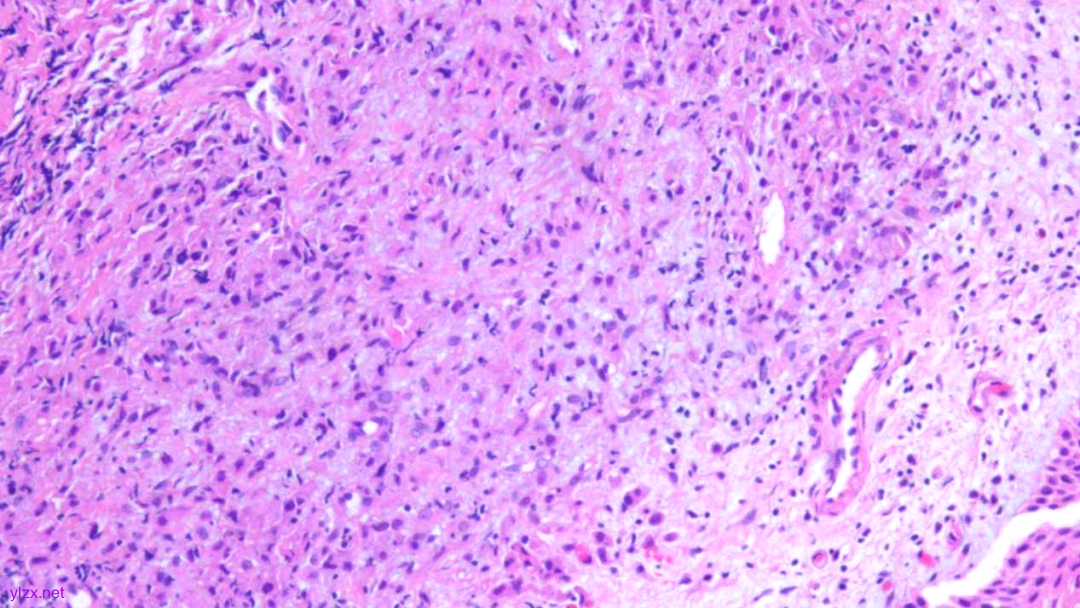

HE:

2.宫颈5点:鳞状上皮下间质内见少量异型细胞巢,核增大,深染,浆红染,少量细胞浆内见黏液,印戒样;宫颈管搔刮组织:见血凝块、宫颈内膜组织,间质见异型细胞条索,形态同宫颈5点。

间质内见异型细胞巢,核增大,深染

间质内见异型细胞条索,核增大,深染,浆红

少量细胞浆内见黏液,印戒样

瘤细胞核偏位,浆红染

高倍瘤细胞见红色核仁